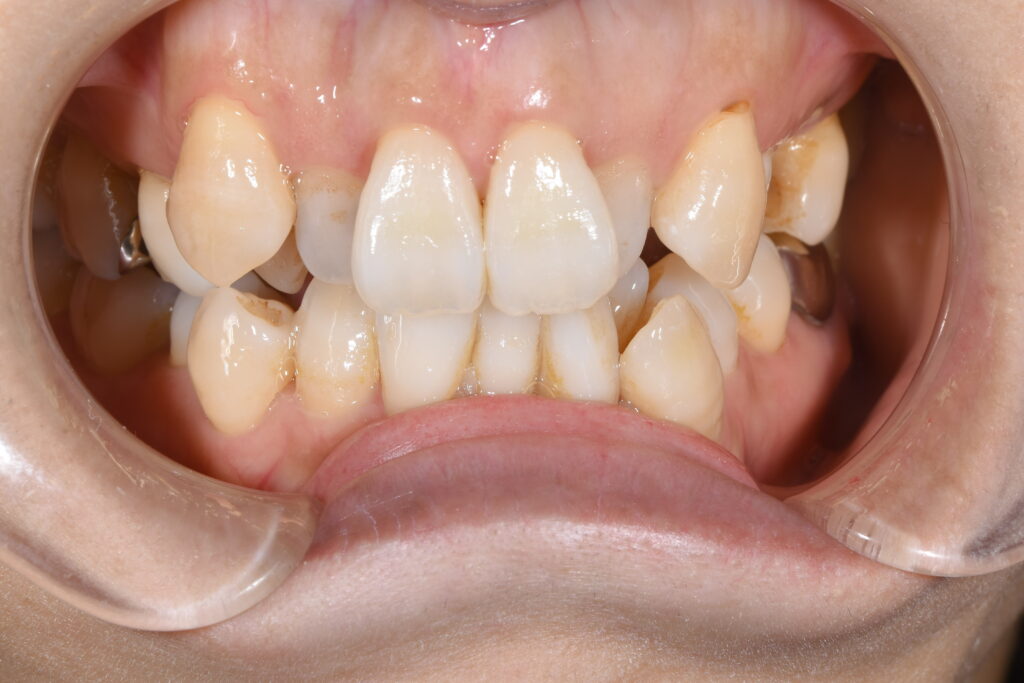

まずは矯正開始前の状態です。

写真が暗くて申し訳ございません。

【矯正開始前】

この患者様の問題点を以下に列挙します。

【問題点】

①歯のががたつきが強く、清掃困難な状態である。

②かみ合わせに問題があり、左上5番目の歯が歯周病で保存困難となったため、抜歯が必要となった。

③歯を並べるスペースが窮屈であり、スペース獲得のため便宜的な抜歯治療が必要である。

大まかに上記3点となります。

今回のように、下の歯のがたつきが顕著な場合、インビザライン(マウスピース)のみで歯並びを改善するよりも、針金を併用する治療も治療計画として考えましたが、患者様ご希望にて、針金は一切使用せず、インビザラインのみで矯正治療を行うこことなりました。